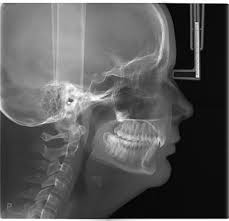

КТ создает трехмерную модель челюсти, выявляя скрытые патологии, которые невидимы на обычном рентгене.

Для компьютерной диагностики в нашей клинике используется немецкий дентальный томограф Orthophos S 3D

Он позволяет получать высококачественные цифровые рентгеновские изображения челюстно-лицевой области в трех взаимно перпендикулярных плоскостях (фронтальной, сагиттальной и аксиальной) с соблюдением норм радиационной безопасности.